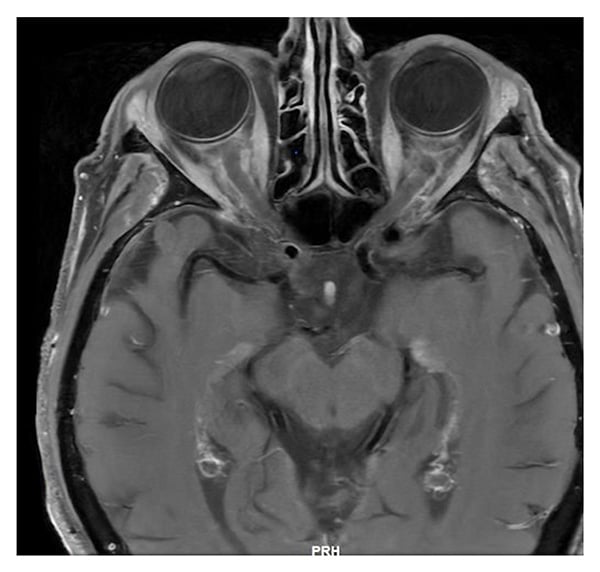

Magnetic resonance imaging (MRI) of the orbit and brain (Figures 1 and 2) revealed mild soft-tissue fullness surrounding the frontal branches of both superficial temporal arteries, suggestive of temporal arteritis. Marked superficial enhancement with fullness of the intraorbital segments of both optic nerves with surrounding fat reticulation was consistent with optic perineuritis. Serologic testing for tuberculosis, syphilis, sarcoidosis, immunoglobulin G4 (IgG4)-related disease, and monoclonal gammopathy was unremarkable.

Figure 2: MRI of the orbits: axial T1 post-contrast shows fullness of intraorbital ocular nerves, with surrounding fat reticulation.